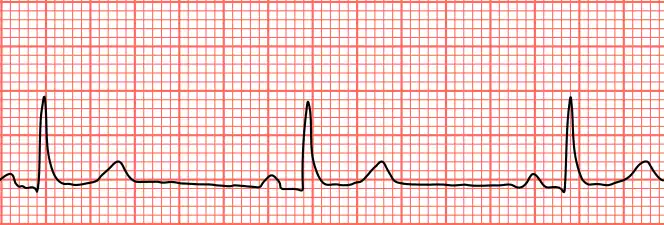

| Sinus bradycardia seen in lead II with a heart rate of about 50BPM | |